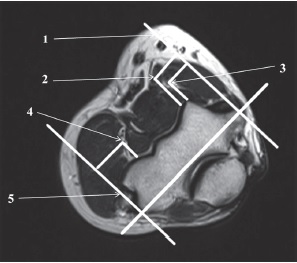

На МРТ ЛС на II уровне в аксиальной проекции измеряли расстояния от лучевого и срединного нервов и плечевой артерии до передней границы тени плечевой кости. Также от вышеупомянутых структур замеряли расстояния до УЛЭЛ и УМЭЛ (рис. 5).

Рис. 5. МРТ локтевого сустава, аксиальная проекция: 1 — условная медиальная эпикондилярная линия; 2 — плечевая артерия; 3 — срединный нерв; 4 — лучевой нерв; 5 — условная латеральная эпикондилярная линия

Результаты клинического исследования

В ходе МРТ-исследования ЛС в аксиальных проекциях на II уровне измеряли расстояния от сосудисто-нервных структур (лучевой и срединный нервы, плечевая артерия) до передней границы тени плечевой кости, а также от лучевого нерва до УЛЭЛ и от срединного нерва и плечевой артерии до УМЭЛ (табл. 4).